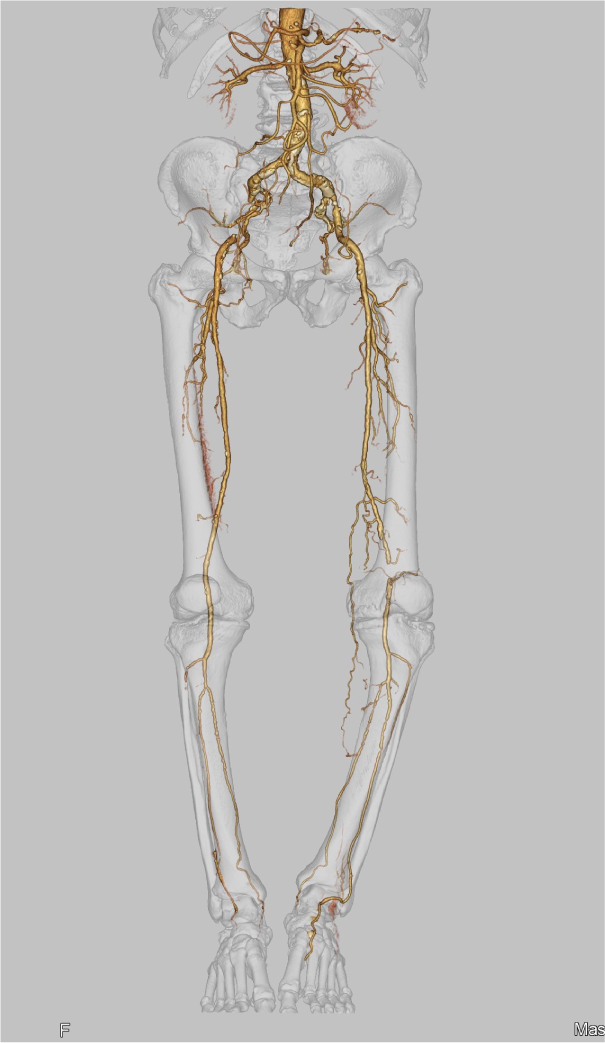

CANON(旧:東芝)社製の80列マルチスライスCTを設置し、胸部・腹部の撮影はもちろん、心臓CTや大腸CT、下肢3DCTといった専門性の高い撮影も行っています。最新のザイオワークステーションを用いて、3D画像作成、心臓解析、大腸の仮想内視鏡検査などを行っています。また、近隣の医療施設からのCT撮影依頼にも対応しており、日々たくさんご利用いただいております。被ばく線量の低減に配慮するとともに、患者さんに合った適切な線量で撮影を行うように心がけています。

前腕CT画像 下肢CT画像